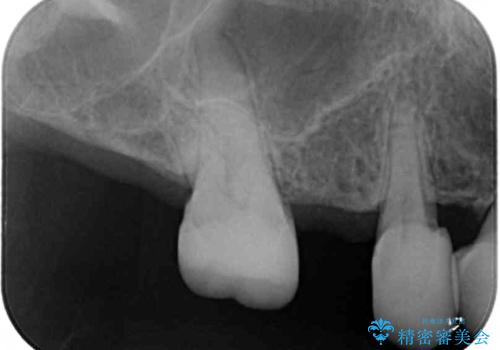

- 虫歯や歯の欠損を放置していることを気にして来院された患者様です。

下顎には抜歯が必要な歯があったため、抜歯後に治癒を待ち、上顎とともにオールセラミックブリッジにて補綴治療を行うこととしました。